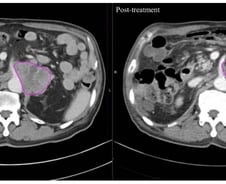

몸속 온도를 '암이 싫어하는 온도(40~43도)까지' 끌어올려 암을 죽이는 '고주파 온열치료'는 새로운 암 치료법 중 하나로 꼽힌다. 이런 가운데 고주파 온열치료를 받은 암 환자들이 방사선 치료받은 환자들보다 암 덩어리가 더 빠르고 효과적으로 줄어든 사실이 국내 '빅5' 병원인 서울성모병원의 연구 결과로 나와 눈길을 끈다. 24일 국제바이러스연구연합(IVRA) 조직위원회에 따르면 장홍석 서울성모병원 방사선종양학과 교수 연구팀은 2019년 1월부터 2022년 3월 말까지 고온 온열치료 환자 20명과 방사선 단독 치료 환자 20명 등 전이성 복부 림프절 치료 환자 총 40명을 대상으로 컴퓨터 단층촬영(CT) 이미지를 모았다. 그리고서 치료 전후 종양 괴사의 변화를 관찰하는 지표(하운스필드 단위·Hounsfield Unit·HU)값의 변화를 비교해 치료 효과를 평가했다. HU는 CT(컴퓨터 단층촬영)에서 CT 영상의 픽셀마다 부여되는 밀도 값으로 조직의 밀도를 수치화한 것이다. 각 조직이